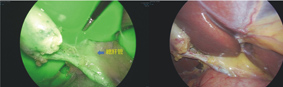

本院是國內非常少數常規進行術中膽道攝影,以評估膽道解剖的醫學中心。因此腹腔鏡膽囊切除的手術成功率是同儕醫院中最高的。但術中的解剖構造必須靠外科醫師利用腹腔鏡手術技巧去合離出來,有時遇到反慢性膽囊發炎的病人,組織沾黏可能會讓手術變得困難甚至危險。ICG 螢光膽道顯影可降低這些風險。在注射大約一小時後,ICG會被分泌到膽汁中,讓我們藉由螢光看到膽管的輪廓,避免誤傷(如圖一)。這樣能夠不用手術剝離組織便可以辨認膽管走向,大幅降低膽道損傷的可能,最大限度促進了病人安全。

圖一、ICG螢光膽道顯影圖